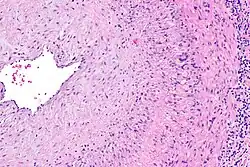

Intermediate magnification micrograph showing giant cell arteritis in a temporal artery biopsy. The arterial lumen is seen on the left. A giant cell is seen on the right at the interface between the thickened intima and mediaH&E stain

The gold standard for diagnosing temporal arteritis is biopsy, which involves removing a small part of the vessel under local anesthesia and examining it microscopically for giant cells infiltrating the tissue.[23] However, a negative result does not definitively rule out the diagnosis; since the blood vessels are involved in a patchy pattern, there may be unaffected areas on the vessel and the biopsy might have been taken from these parts. Unilateral biopsy of a 1.5–3 cm length is 85–90% sensitive (1 cm is the minimum).[24] Characterised as intimal hyperplasia and medial granulomatous inflammation with elastic lamina fragmentation with a CD4+ predominant T cell infiltrate, currently biopsy is only considered confirmatory for the clinical diagnosis, or one of the diagnostic criteria.[11]